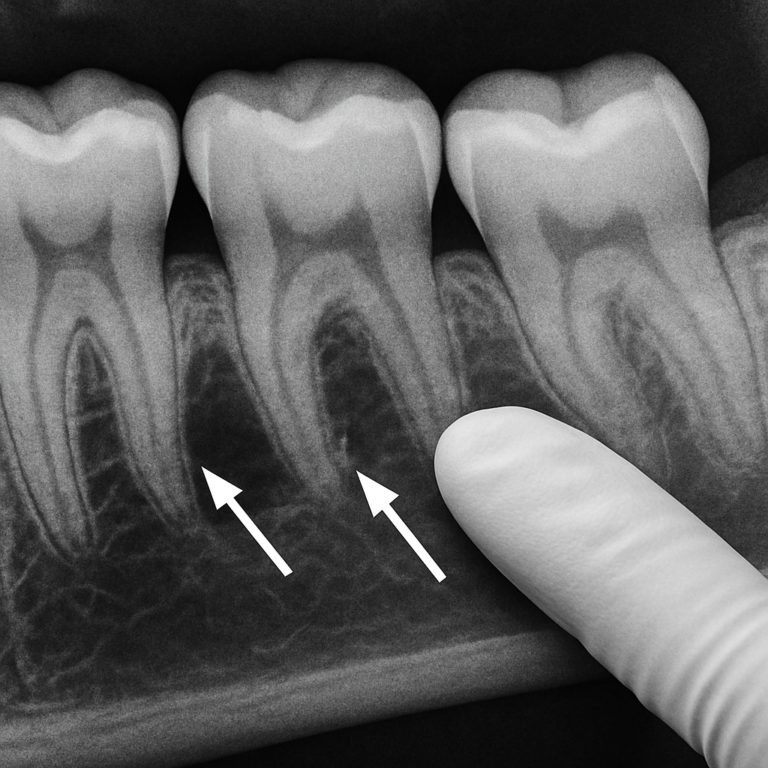

Bone loss from gum disease happens when bacteria under the gumline destroy the bone that holds your teeth. This process can start quietly and progress